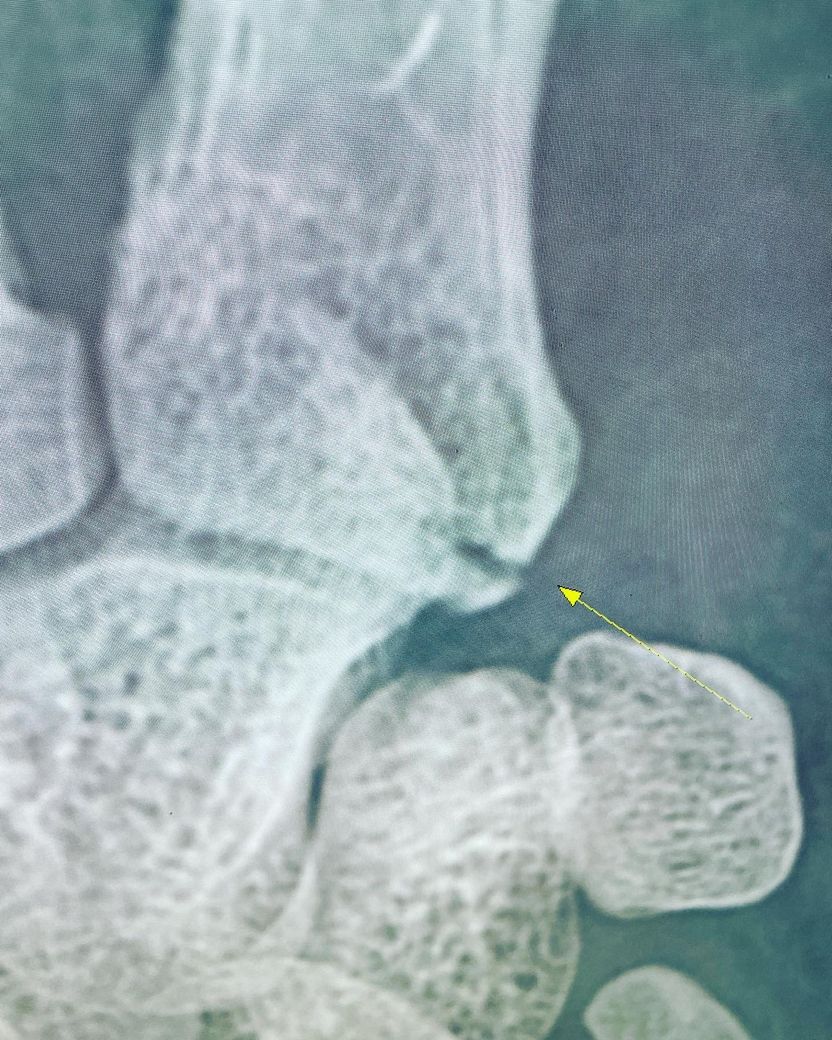

약 두 달 전 (3월 16일) 격투기 운동을 하다가 그라운드상태에서 상대의 등에 오른손이 깔리면서 통증을 느껴 다음 날 정형외과에 방문하여 엑스레이 촬영 결과 오른손 5번 중수골 기저부 골절 진단을 받았습니다.

1주에서 2주사이는 보호대 착용시 통증이 심하여 진통제 복용을 하였으며 3주차부터는 통증이 거의 없어 괜찮은가 하는 생각에 근무중에 보호대를 풀고 손을 쓴다거나 하는 경우가 빈번했습니다 손을 쓰고 난 후 보호대를 착용하면 다시 욱신거리는 통증이 생겼다가 일정시간이 지나면 괜찮아지는것이 반복되었고 마지막으로 병원 엑스레이 촬영시(5월10일-약 7주경과) 뼈가 아직도 붙지 않았다고 하였습니다.

현재 골절 후 유합이 잘 이루어지고 있지 않은 상태이므로 수술적 치료도 고려해 볼 수 있으나 해당 주치의와 상의하여 판단하는 것이 좋겠습니다. 유합이 제대로 이루어지기 전까지 움직이게 되면 회복에 악영향을 줄 수 있으니 상의후에 필요시 완전히 캐스트로 고정하는 것도 가능한지 상의해보시는 것도 좋을 것 같습니다.

손을 사용하셔서 불유합이 생긴것 같습니다. 이런경우 완전 고정하고 조금 더 기다려보거나 체외충격파로 뼈 유합을 자극해볼 수 있습니다.